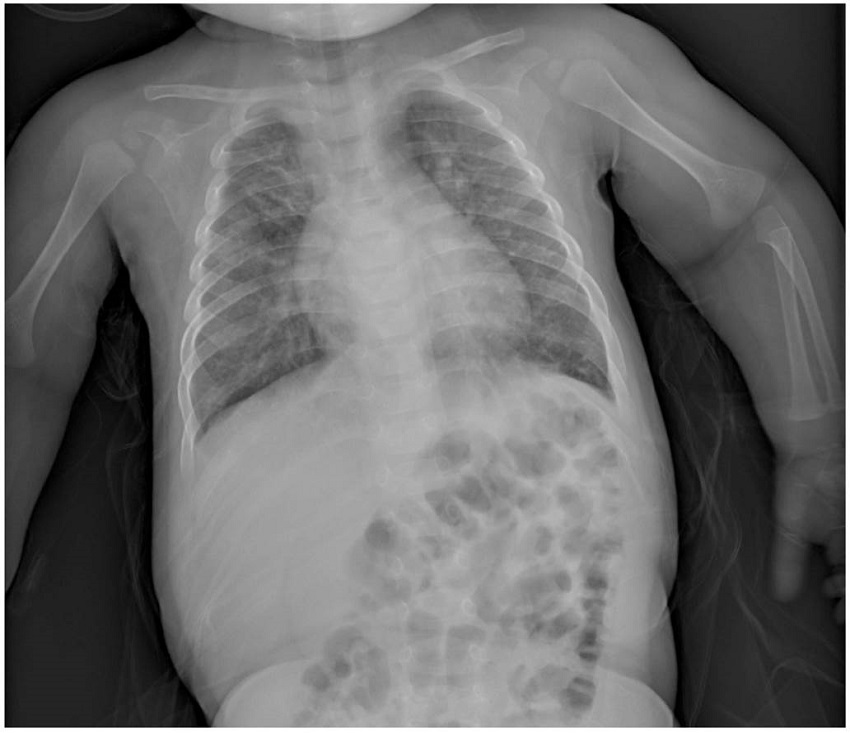

Se decidió un cambio de tratamiento a ceftriaxona intravenosa, se realizó un sondaje nasogástrico para la alimentación enteral de la paciente y se mantuvo con estrecha vigilancia y monitorización de constantes. Tras 15 días de ingreso hospitalario, finalmente la paciente progresa de forma favorable. En la radiografía de control se observa que persisten engrosamientos peribronquiales y un ligero aumento difuso de la densidad pulmonar en vidrio deslustrado, pero con mejoría y desaparición de la consolidación subsegmentaria en el campo medio-superior izquierdo (figura 3). Con la estabilización de constantes con saturaciones basales del 96%, afebril y con buena tolerancia oral, se decide el alta hospitalaria con control telefónico de la paciente por Atención Primaria.